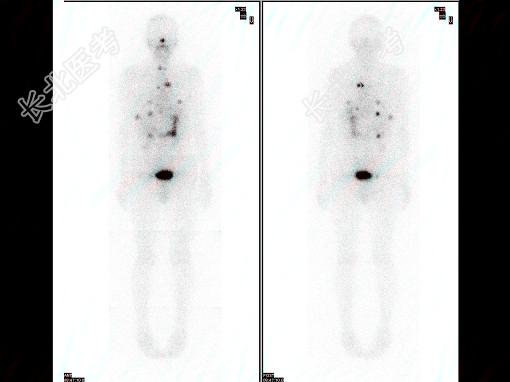

多项选择题63岁男性,甲状腺滤泡状癌术后3年, 行I全身显像及SPECT/CT图像融合如图,正确的诊断是 ( )

A、多发肺、脑转移

B、有骨转移

C、无骨转移

D、多发肺转移

E、未见明显转移灶